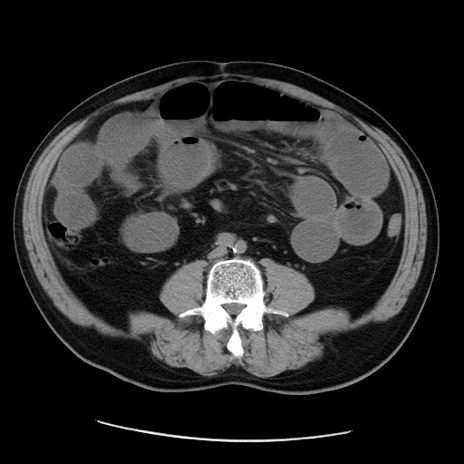

症例20(横断像)

【症例】 60歳代男性

【主訴】 腹部膨満、嘔吐

【現病歴】5日前頃より倦怠感を認め食事量減少し4日前の朝嘔吐、食事摂取困難となった。 3日前近医受診し点滴施行され整腸剤などを処方された。 当日他院を受診し、腹部膨満著明、炎症反応の上昇(CRP10.8、WBC11200)あり、紹介受診となる。

【身体所見】 意識JCS1 受け答えがはっきりしないBP 111/57mHg、 P 67bpm、、BT35.2°C、SpO2 97%(RA)、 腹部:膨隆、打診で鼓音あり、全体的に圧痛有り、腸蠕動音(-)、反跳痛ははっきりせず。

【データ】WBC 11400、CRP 14.20